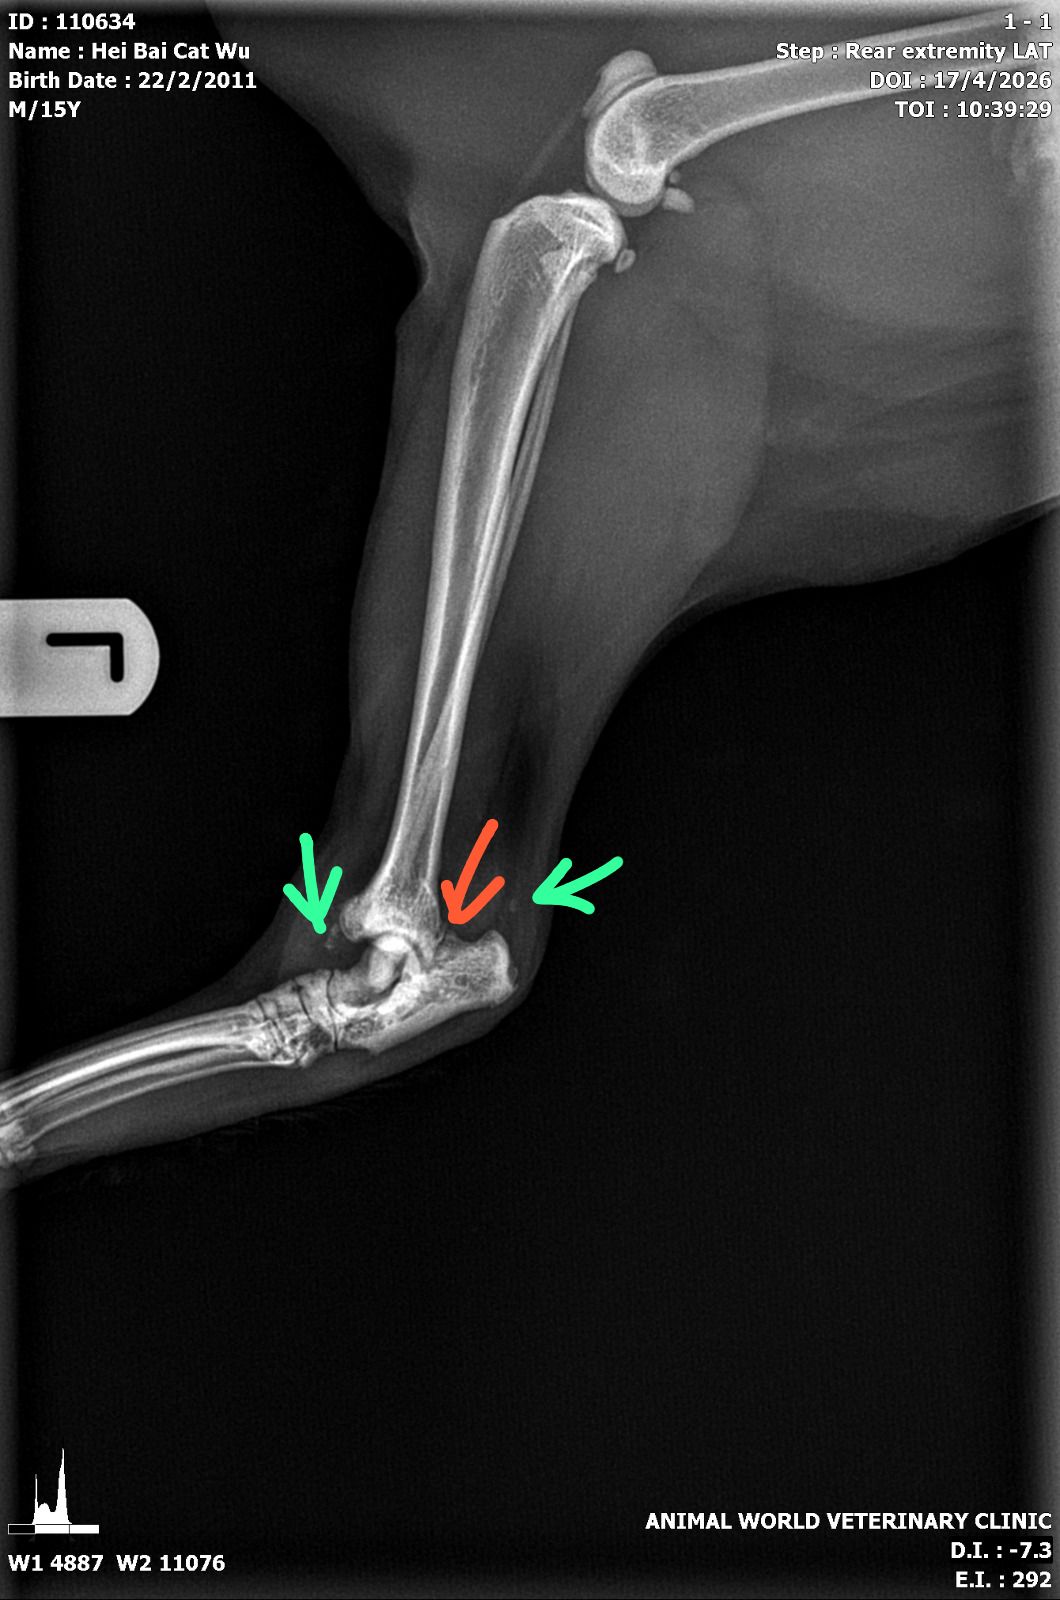

– xrays L and R hock all have evidence of marked arthritis and there is suspected fracture at the hinge of the hock (both left and right) so suspect is obesity related

“Left hock

Green arrows – lots of osteophytes/arthritis

Red arrow – suspected fractured site but ideally need VD view

General bone density of hock bone more porous than usual”